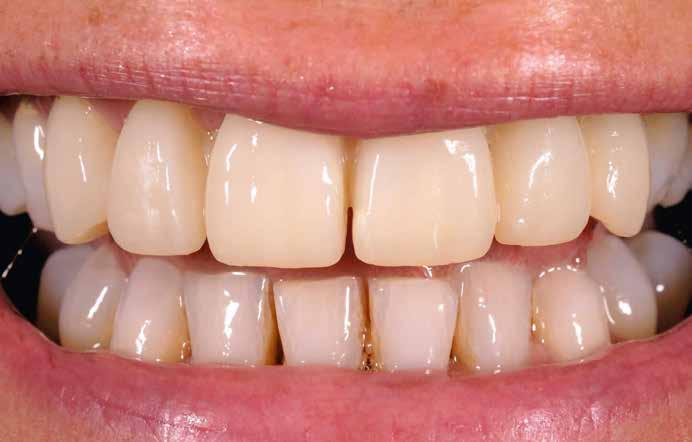

Elhagyott frontfogak, megtámadott parodoncium: a páciens kiindulási helyzete több mint nehéznek bizonyult. Yuki Momma és dr. William C. Heggerick, szerzőink, bemutatják, hogyan állítható helyre a harmónia a négy frontfog ellátásával.

A felső frontfogak állapota elhanyagolt, a parodontális struktúrák részben erősen károsodottak, VMK korona az 12 zónában, az ínyszél szürke, fekete approximális háromszögek… vörös-fehér esztétikáról nem is beszélhetünk (1. kép). Így jelentkezett a hölgypáciens a Weston Dental Specialists Group rendelőben. Elvárásai magasak voltak. A defektusok kezelését, a gingiva lefutásának korrigálását kívánta. Gyorsan világossá vált, hogy a megoldást csak a négy frontfog teljes kerámiakoronával való ellátása jelentheti. A jelen eset bemutatja, hogy az IPS e.max ZirCAD Prime segítségével hogyan lehet tiszta, tetszetős és esztétikus mosolyt létrehozni.

1. kép: Kiindulási helyzet.

A kialakítás tervezése

A páciens aggodalmas volt, hogy ne kapjon túl nagy és szögletes koronákat. A vele folytatott megbeszélések során viaszmintázat, majd annak alapján kulcs készült a mock-uphoz. Ennek segítségével az újonnan készülő pótlás formáját közösen, egyértelműen határozhattuk meg (2. kép).

oka a zománcvastagság változása cervikáltól incizál felé. A dentin, amely erőteljesebb színtelítettségű, mint a zománc, változó erősséggel tűnik át a háttérből, és tipikus karaktert kölcsönöz a fognak. Az 12-es fogon látható VMK korona (fémkerámia – a ford.) nem felelt meg ezeknek a követelményeknek, és élettelen testként tűnt fel a front megjelenésében. A 8. kép az IPS e.max ZirCAD Prime koronák próbájánál készült. Jól látható, hogy a folyamatos szín- és transzlucencia átmenet ideálisan imitálja a természetes fogakét, és plasztikus benyomást kelt. Az egyedi jellegzetességek, mint

a mamelonok és a kiemelt zománcrepedések élettelibbé teszik a koronákat.

Gingivára fókuszálás

A gingiva kontúr lefutása szintén fontos az esztétikus megjelenés szempontjából. A teljesen szimmetrikus restaurációk általában természetellenesen hatnak, az árkádok itt látható enyhe aszimmetriája természetes hatást

keltett. Az egyébként ideális tipikus formájú koronák esztétikailag optimális gingivakialakítást hoznak létre, a VMK korona kicserélése egyenletes fénytovábbítást tett lehetővé a papilláktól a korona felé és fordítva is. Míg a próba során még minimális sötét approximális háromszögek láthatók voltak, a végleges beragasztásra (Variolink Esthetic, Ivoclar Vivadent) már eltűntek (9. kép). A gingiva tökéletesen hozzásimult az IPS e.max ZirCAD Prime restaurációhoz.

Összefoglalás

Anyagválasztásunk újra tökéletesnek bizonyult. Kiemelkedő természetes hatása folytán akár leplezetlen IPS e.max ZirCAD Prime anyaggal is nagyon jó esztétikai hatású monolit restaurációk készíthetők. Itt az optimális alapot képezte, hogy leplező- és festékanyagainkkal elérhessük a kívánt hatást: hibátlan mosolyt és természetes szépséget. A páciens nagyon elégedett a kezelés eredményével – akárcsak mi magunk (10. kép).